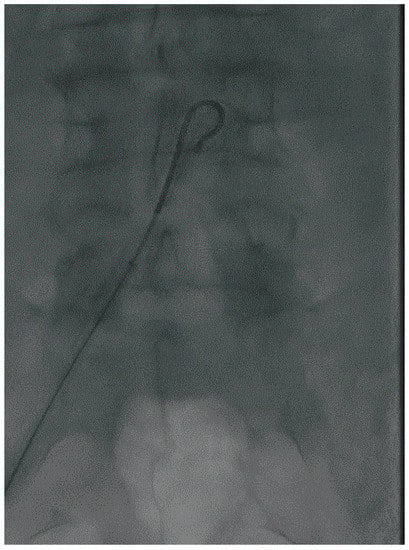

2. Define the Approach

3. Crossing the Lesion